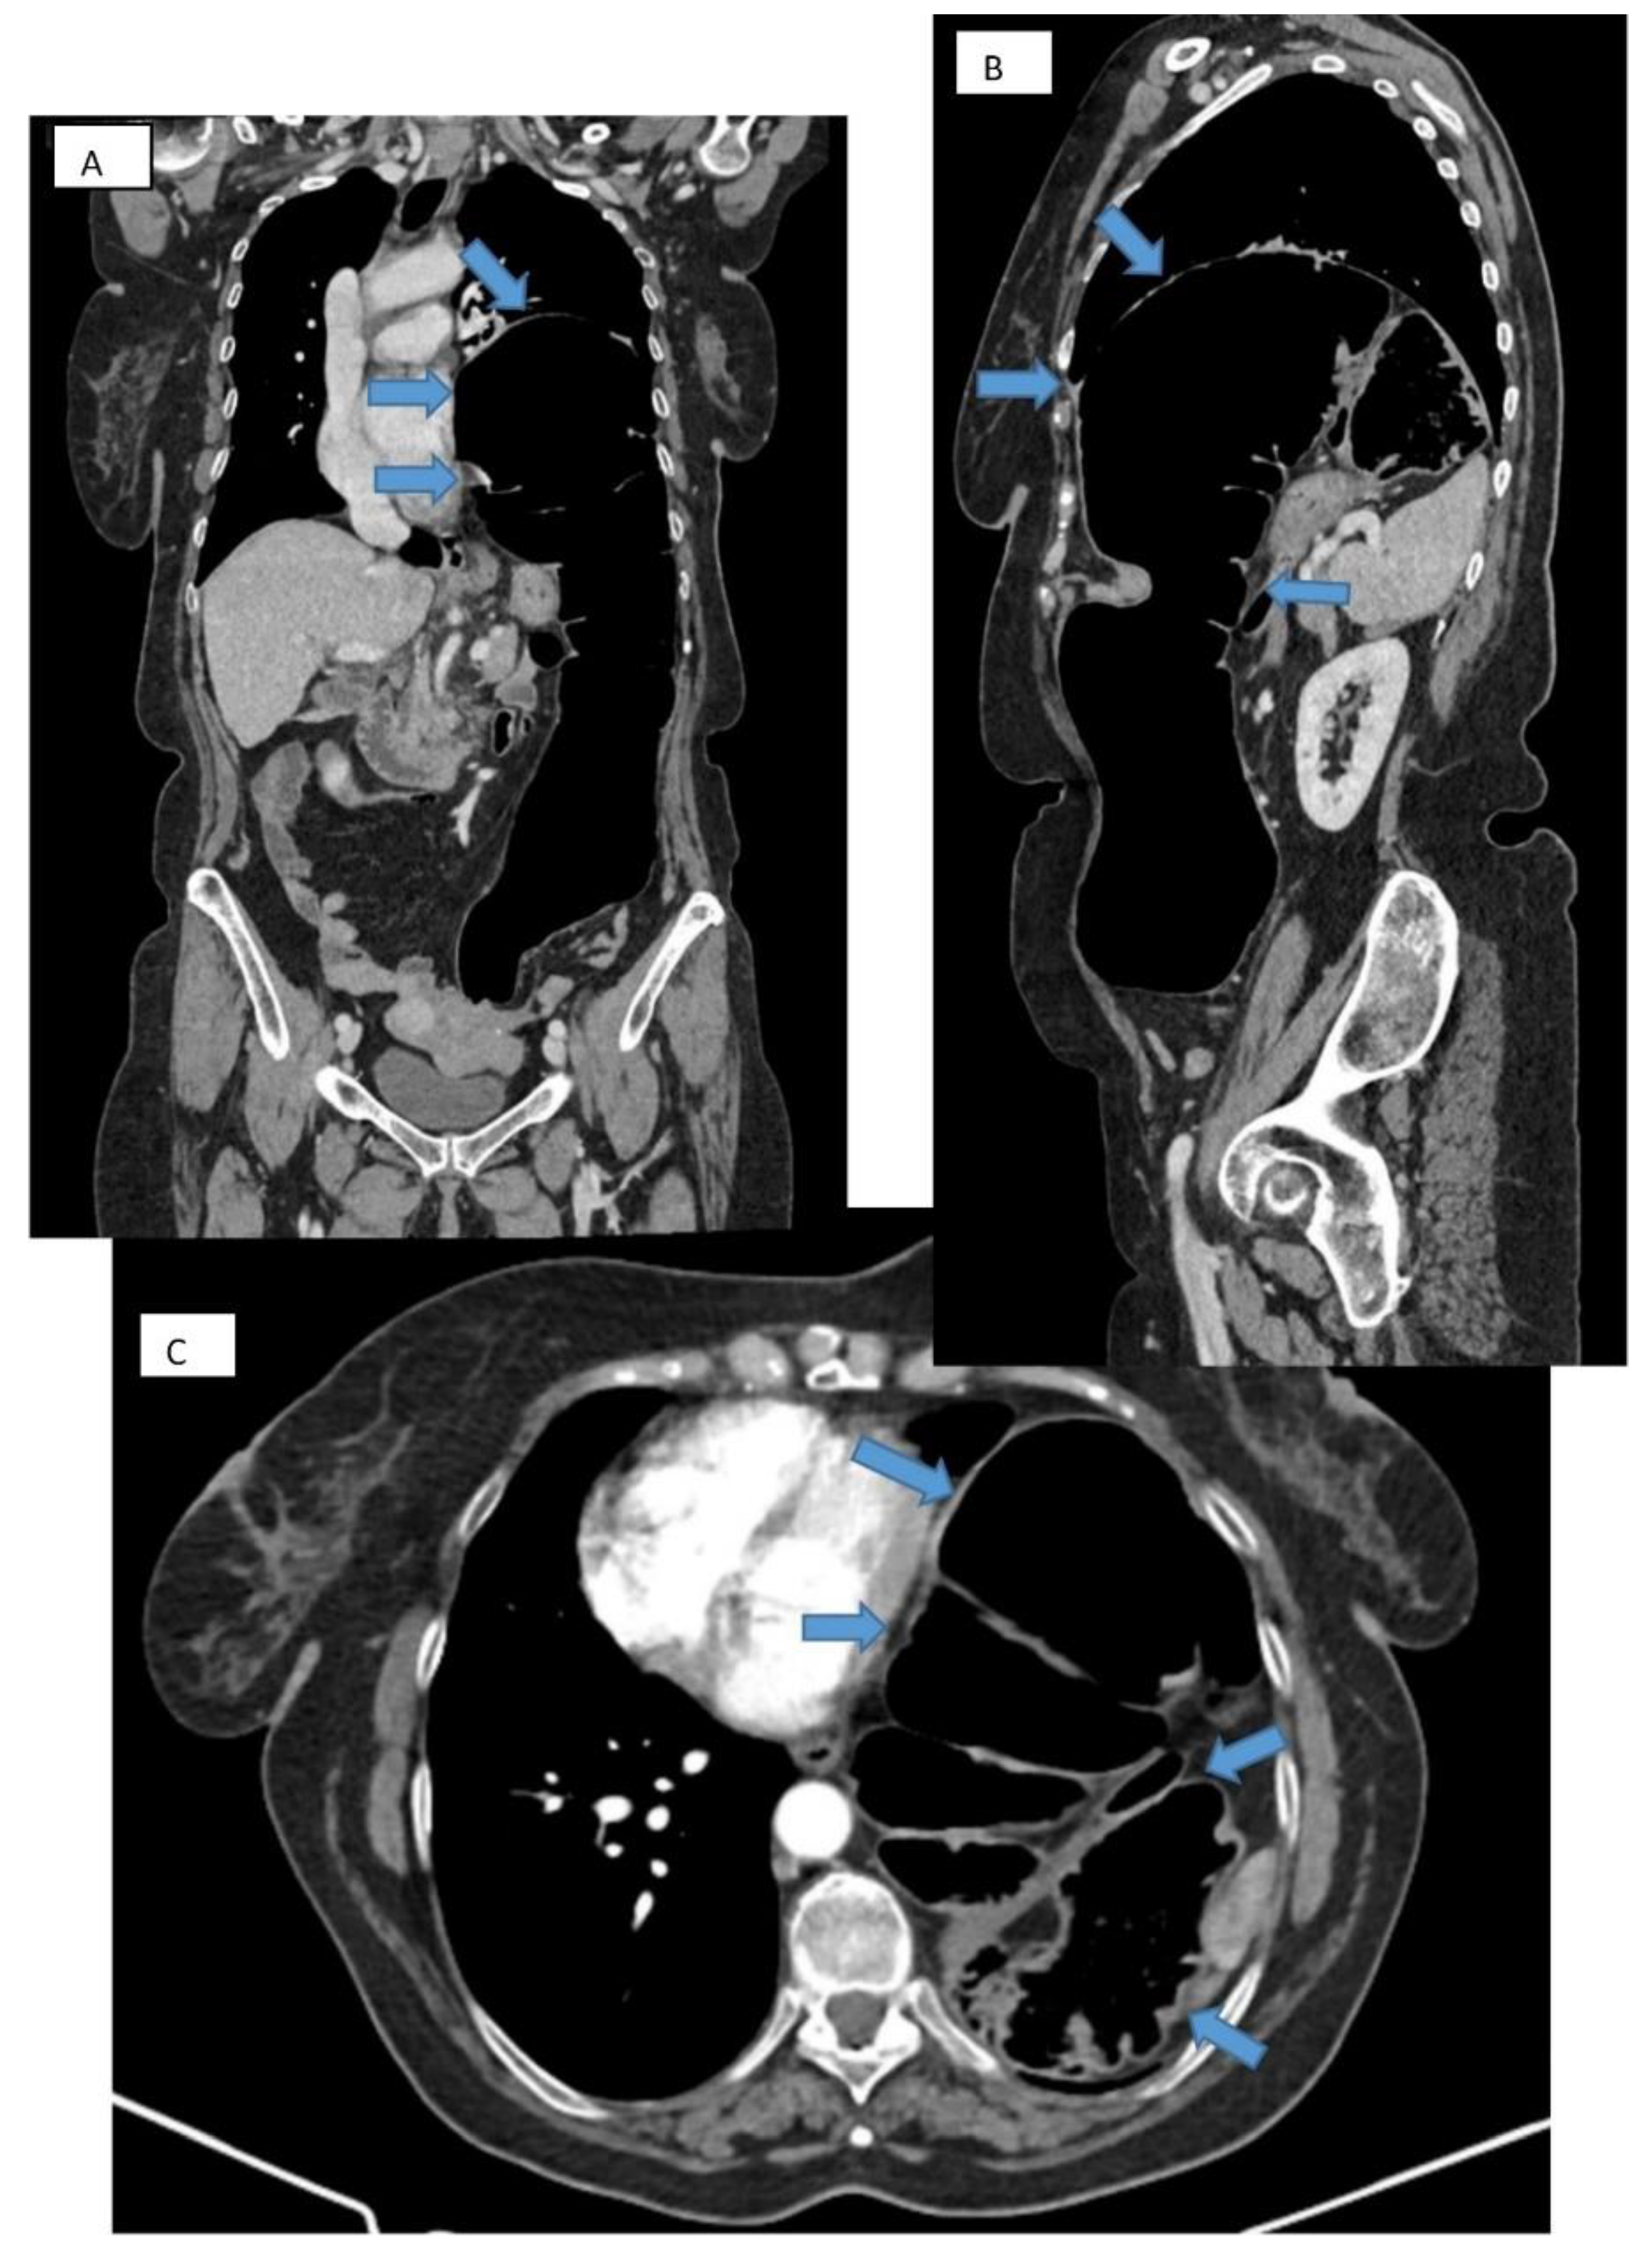

Chest X-ray is most often the first radiological investigation performed in these patients (90%). Chest and abdominal X-ray is recommended to be performed in multiple incidences, including the Trendelenburg position. Specific radiological signs are opacification of the lung bases, especially of the posterior fields depending on the contents of the hernial sac (Figure 1), intrathoracic localization of the abdominal viscera, and left hemidiaphragm elevation (more than 4 cm) with or without atelectasis. In general, diagnosis is more difficult when the hernial orifice is located on the right hemidiaphragm.

Computed tomography refines the diagnosis by accurately identifying the location, dimensions of the defect, the hernial sac, and the intrathoracic herniation of viscera [17] (Figure 3A–C). Tomographic imaging represents a key element in establishing therapeutic decisions. CT has a sensitivity for left-sided injuries that is greater (78–100%) than for right-sided injuries (50–79%). The presence of a pleural effusion, a pulmonary atelectasis, simultaneously with the identification of digestive viscera at the thoracic level is revealing for diagnosis.

Figure 3. CT thorax with contrast. Frontal (A), sagittal (B), and transverse (C) section showing large diaphragmatic defect (Bochdalek hernia) with intrathoracic herniation of the colon.